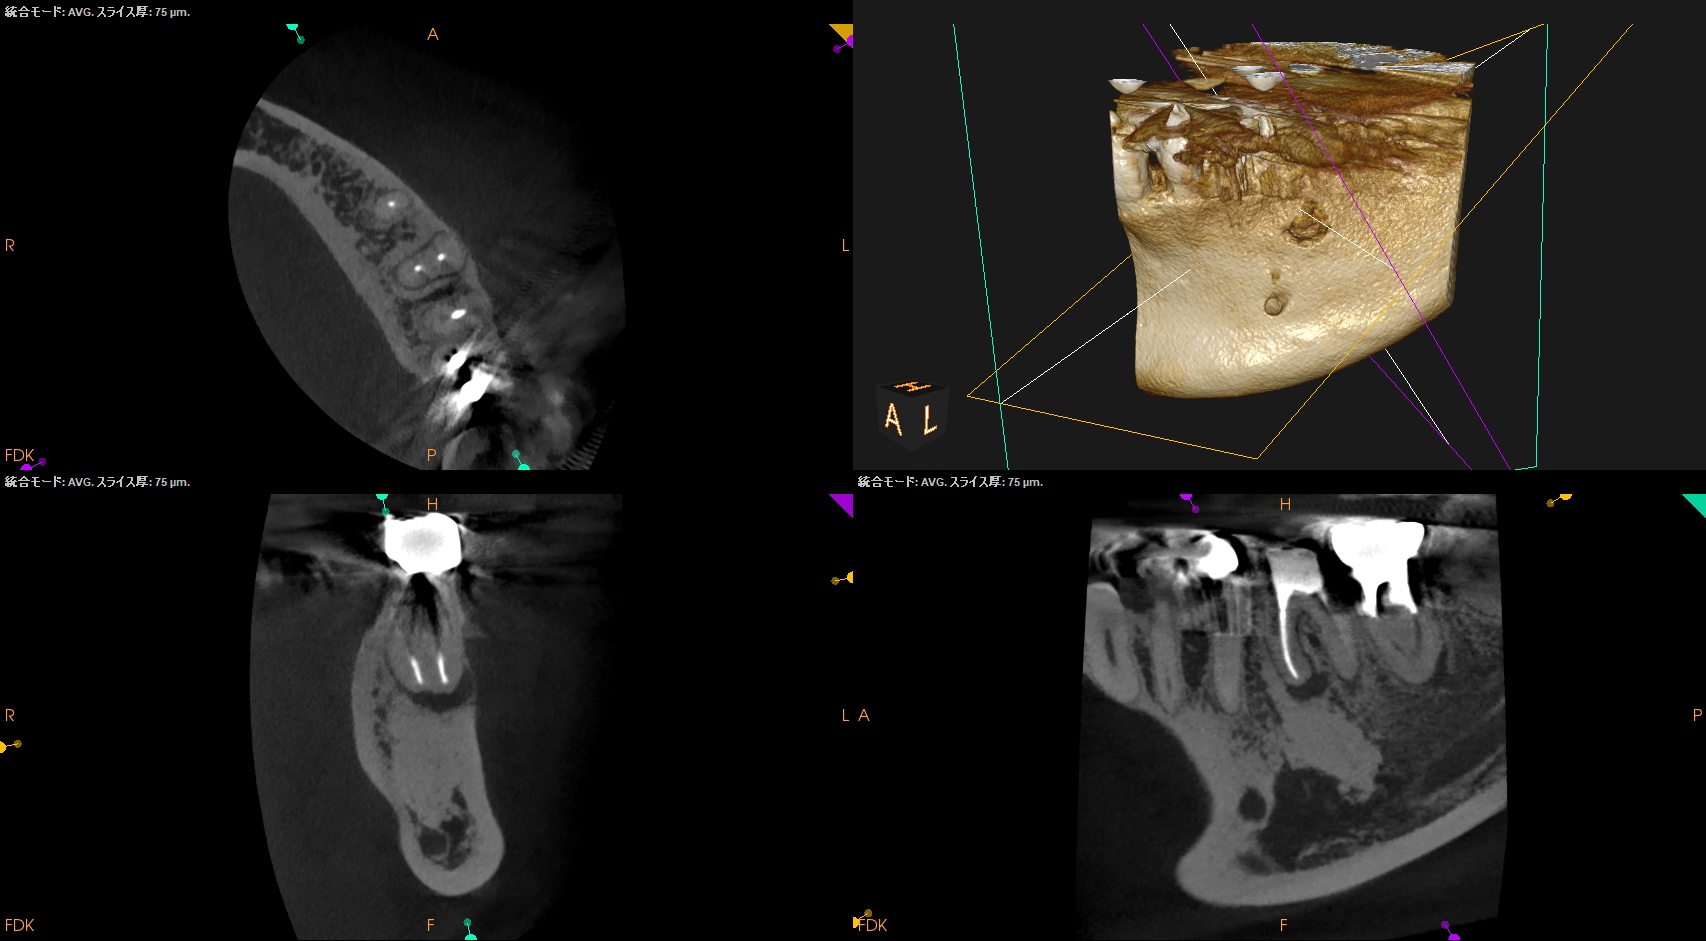

#19 Re-RCT 1yr recall(2026.1.13)

#19

MB

ML

D

術前に大きな根尖病変が存在していたM根のそれは消失はしていないが大幅に縮小し、

術前に根尖病変がなく再根管形成・充填しなかったD根はやはり依然として根尖病変はできていない。

このケースでも

Selective Root Canal Retreatmentが奏功している。

ということで根尖病変は完全消失はしていないのでまた1年後に経過を見せてもらうことになった。